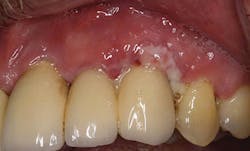

Figure 7: Biofilm/ Inflammation (courtesy of Dr. J. Remien).

Currently, the only air polisher that is proven safe to use on implants is EMS Air-Flow Perio Powder (glycine, 25 microns) with the Perio Implant Tip - used at the beginning of the implant maintenance appointment to remove the biofilm and prevent cross-contamination. Once the implant is exposed to the environment and restored, a salivary pellicle is formed by bacteria for the formation of biofilm. Therefore, the elimination of 85% of biofilm on a daily basis is critical to the overall health of the implant23-25 (Figure 7).